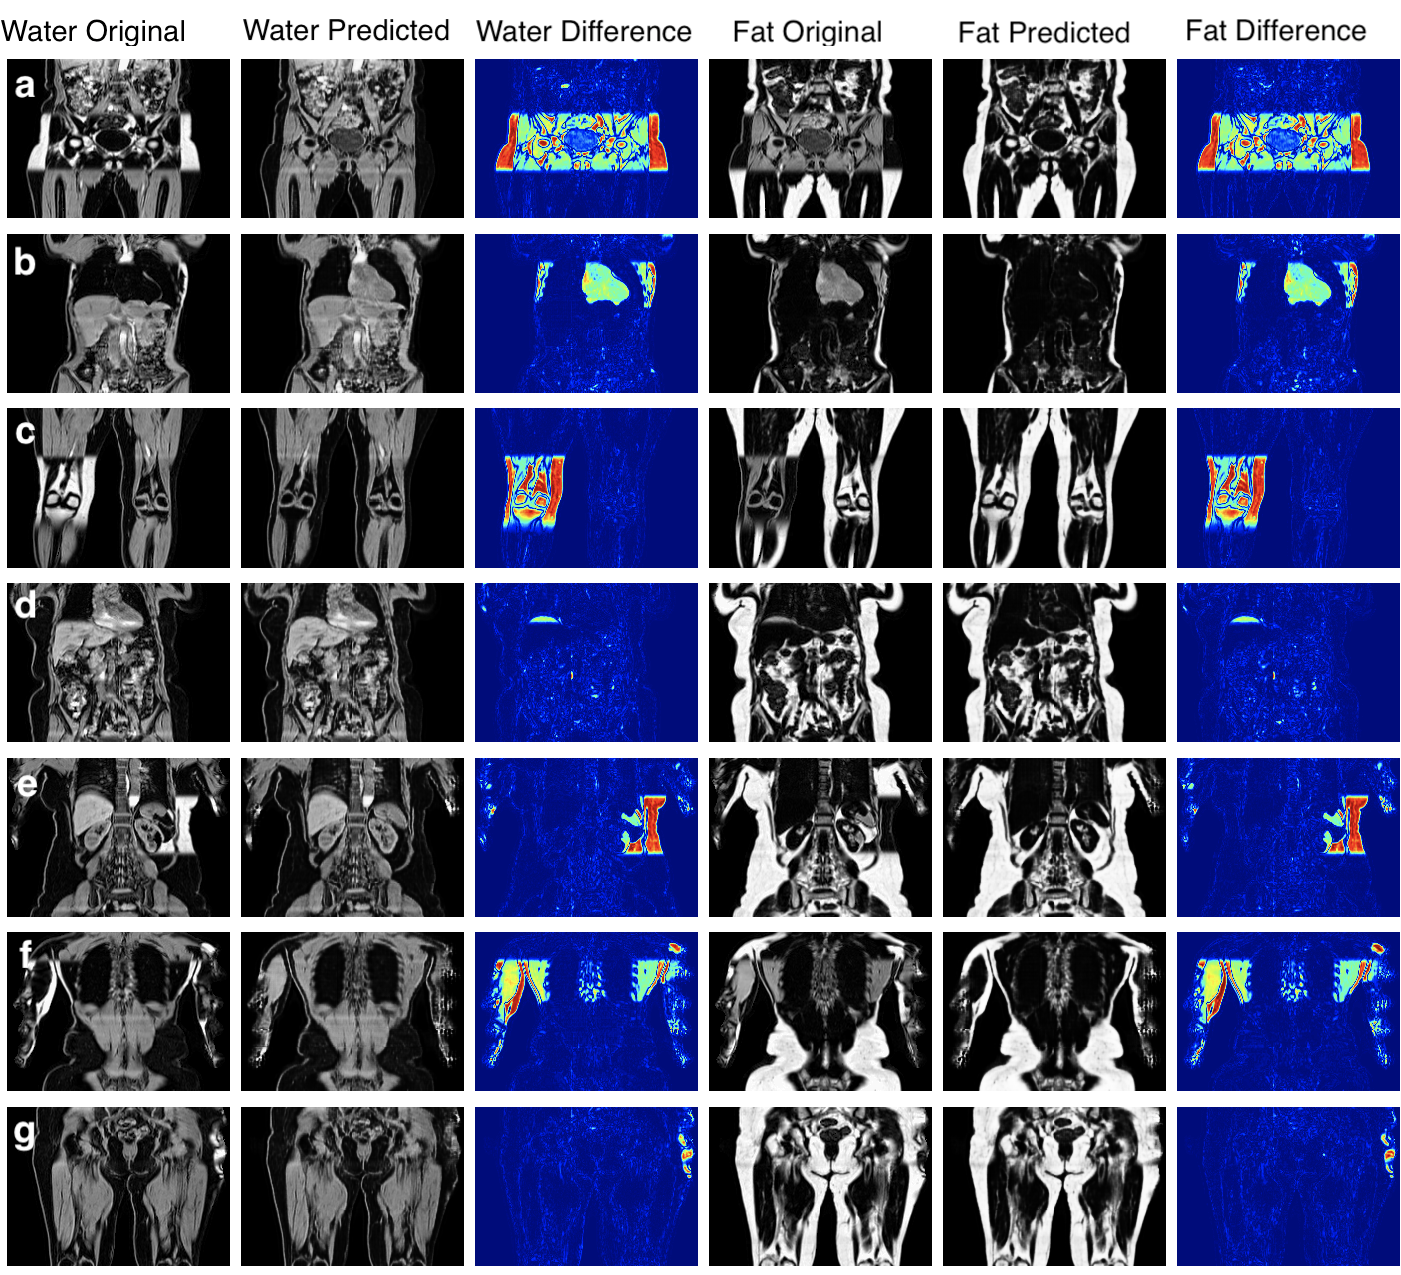

Fig. 3 shows the ground-truth data, predictions and their absolute difference for the fat and water channels of a participant in the testing set. Model predictions and the original data from the scanner for participants affected by various fat-water swaps are provided in Fig. 4. The examples were selected to illustrate the performance of our model in a variety of scenarios: data that are not affected by major swaps, data affected by swaps that cover an entire series in the acquisition (Fig. 4 a, c), as well as data displaying complex partial (Fig. 4 b, d, e) and/or boundary swaps (Fig. 4 f, g). The absolute difference images in columns 3 and 6 of Fig. 4 highlight where the original data have been affected by a fat-water swap in the scanner reconstruction but the model correctly predicted the fat and water channels. Fig. 5 provides examples of 3D segmentations using data that suffered from fat-water swaps (top row) and the segmentation when using our model predictions (bottom row) for the following organs and tissue (from left to right): abdominal subcutaneous adipose tissue, left kidney, spleen, and left/right iliopsoas muscles (red and green, respectively). The predictions shown in Figs. 3 and 4, as well as the underlying volumes used for the 3D segmentations in Fig. 5, are outputs of the final dual-input model, which performed the best across all of our experiments.

We successfully separated fat and water channels for 3D Dixon MRI in our three experiments, where the best model utilises both the in-phase and out-of-phase data as input with L1 loss. We have shown that our method correctly separates and channels and is able to overcome a wide variety of fat-water swaps, including those explicitly excluded from the training data (e.g., swaps that completely cover one of the series acquired, cover half the series in the legs, top-of-the-liver swaps). However, minor fat-water swaps located at the boundary of the field of view or only involving the arms were included in the training data as they occur infrequently and at random anatomical locations. We hypothesise that the infrequency and randomness of these types of swaps in the training data means that the model ignores them when optimising the generator. In Fig. 4, particularly rows e-g, it appears that the model is able to ignore and minimise the effect of the those swaps even though they were almost certainly present in the training data.

Our assessment of false positive rate between the dixonfix method [13] and our method using 50 out-of-sample subjects that were free of swaps, has shown that our model induced zero false positives. On average, the dixonfix method induced 4.29 swaps inside the body, with an average misclassification of voxels per subject, equivalent to an error rate of 0.074% over the entire volume (including background voxels).